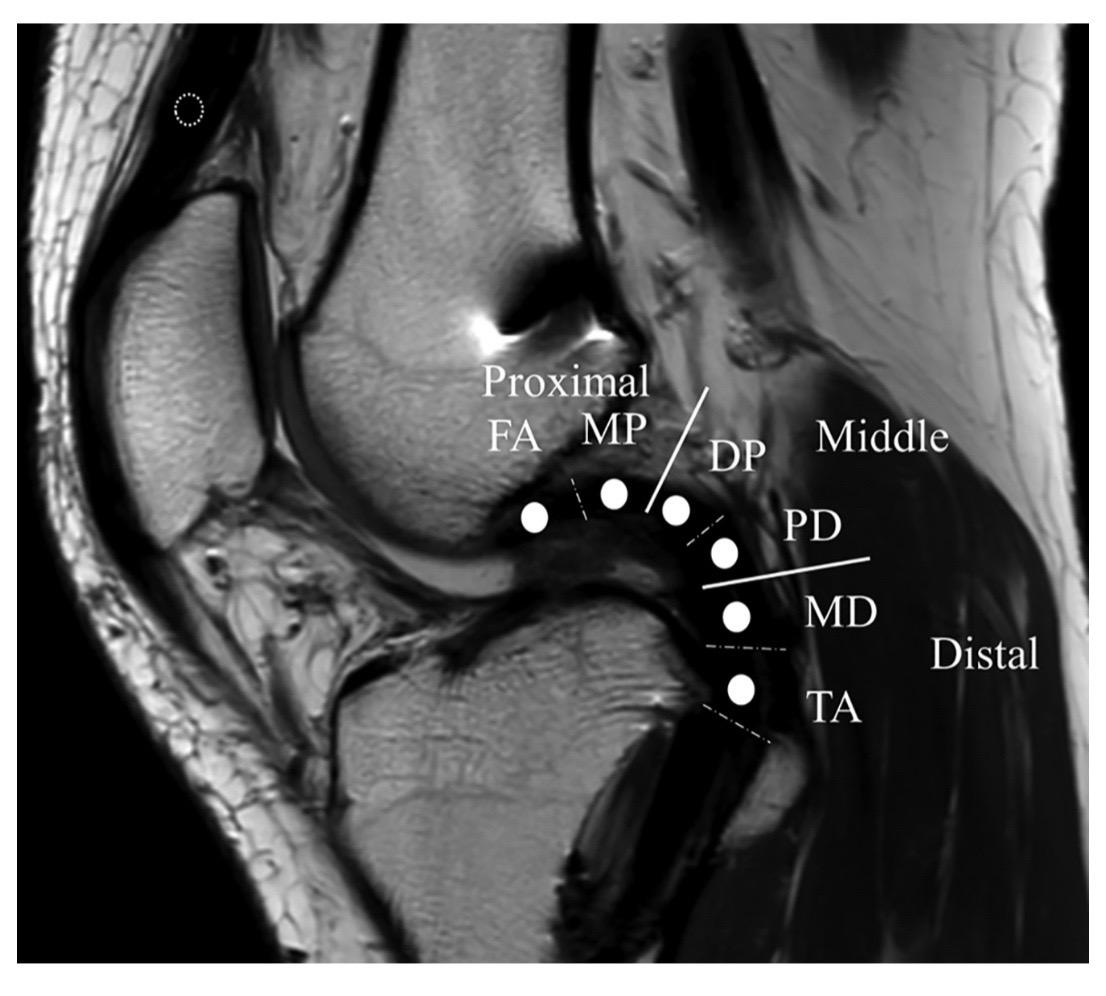

后交叉韧带重建。后交叉韧带(PCL)重建手术中,适当的隧道位置、隧道角度和移植物角度对于维持PCL移植物的稳定性和机械性能至关重要!